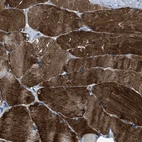

Immunohistochemical staining of human skeletal muscle shows strong cytoplasmic positivity in myocytes.